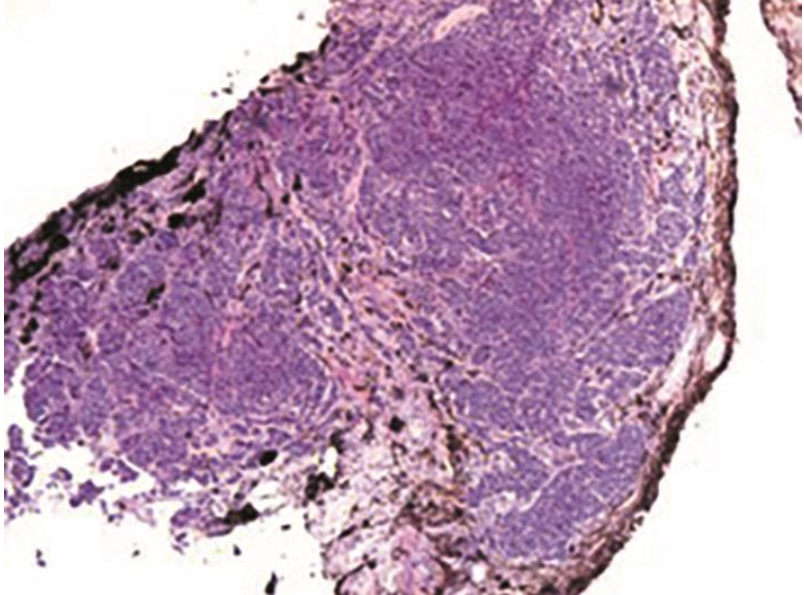

患者女性,49岁,主因“右眼视物模糊1个月余”就诊于首都医科大学附属北京同仁医院眼科。患者自述近1个月余来右眼视物模糊,不伴眼红、眼痛、畏光、眼前黑影遮挡,未行眼科治疗。既往体健,否认眼部及全身病史、手术外伤史、家族遗传病史、食物药物过敏史。查体:双眼视力1.0,眼压右眼12mmHg,左眼15mmHg。右眼结膜无充血,角膜清,前房中深,瞳孔圆,直径约3mm,对光反射存在,颞上方虹膜实性占位性病变,大小约3mm×3mm,瘤体色白,表面覆盖大量色素、表面少量出血及白色渗出,前房可见白色絮状渗出,晶状体透明,余前节未见明显异常(图1),左眼前节未见明显异常。双眼视盘界清色正,视网膜血管走行正常,视网膜平伏,未见出血、渗出等异常表现。辅助检查:双眼OCT未见明显异常。初步诊断:右眼虹膜占位,性质待查(炎症?)。予患者颞上结膜下注射妥布霉素2万单位+地塞米松3mg,每天1次×3天;右眼妥布霉素地塞米松滴眼液,每天4次点眼抗炎治疗。为进一步明确病因及诊断,同时完善眼部UBM(图2),CDI(图3),眼眶MRI、胸部X线、血尿常规、C反应蛋白、生化常规、凝血四项、免疫四项、T-SPOT结核杆菌γ-干扰素释放试验、抗链O、抗核抗体(ANA)、TORCH特异性抗体检查。

图1 首诊右眼前节照相可见瘤体色白,表面覆盖大量色素、表面少量出血及白色渗出,前房白色絮状渗出